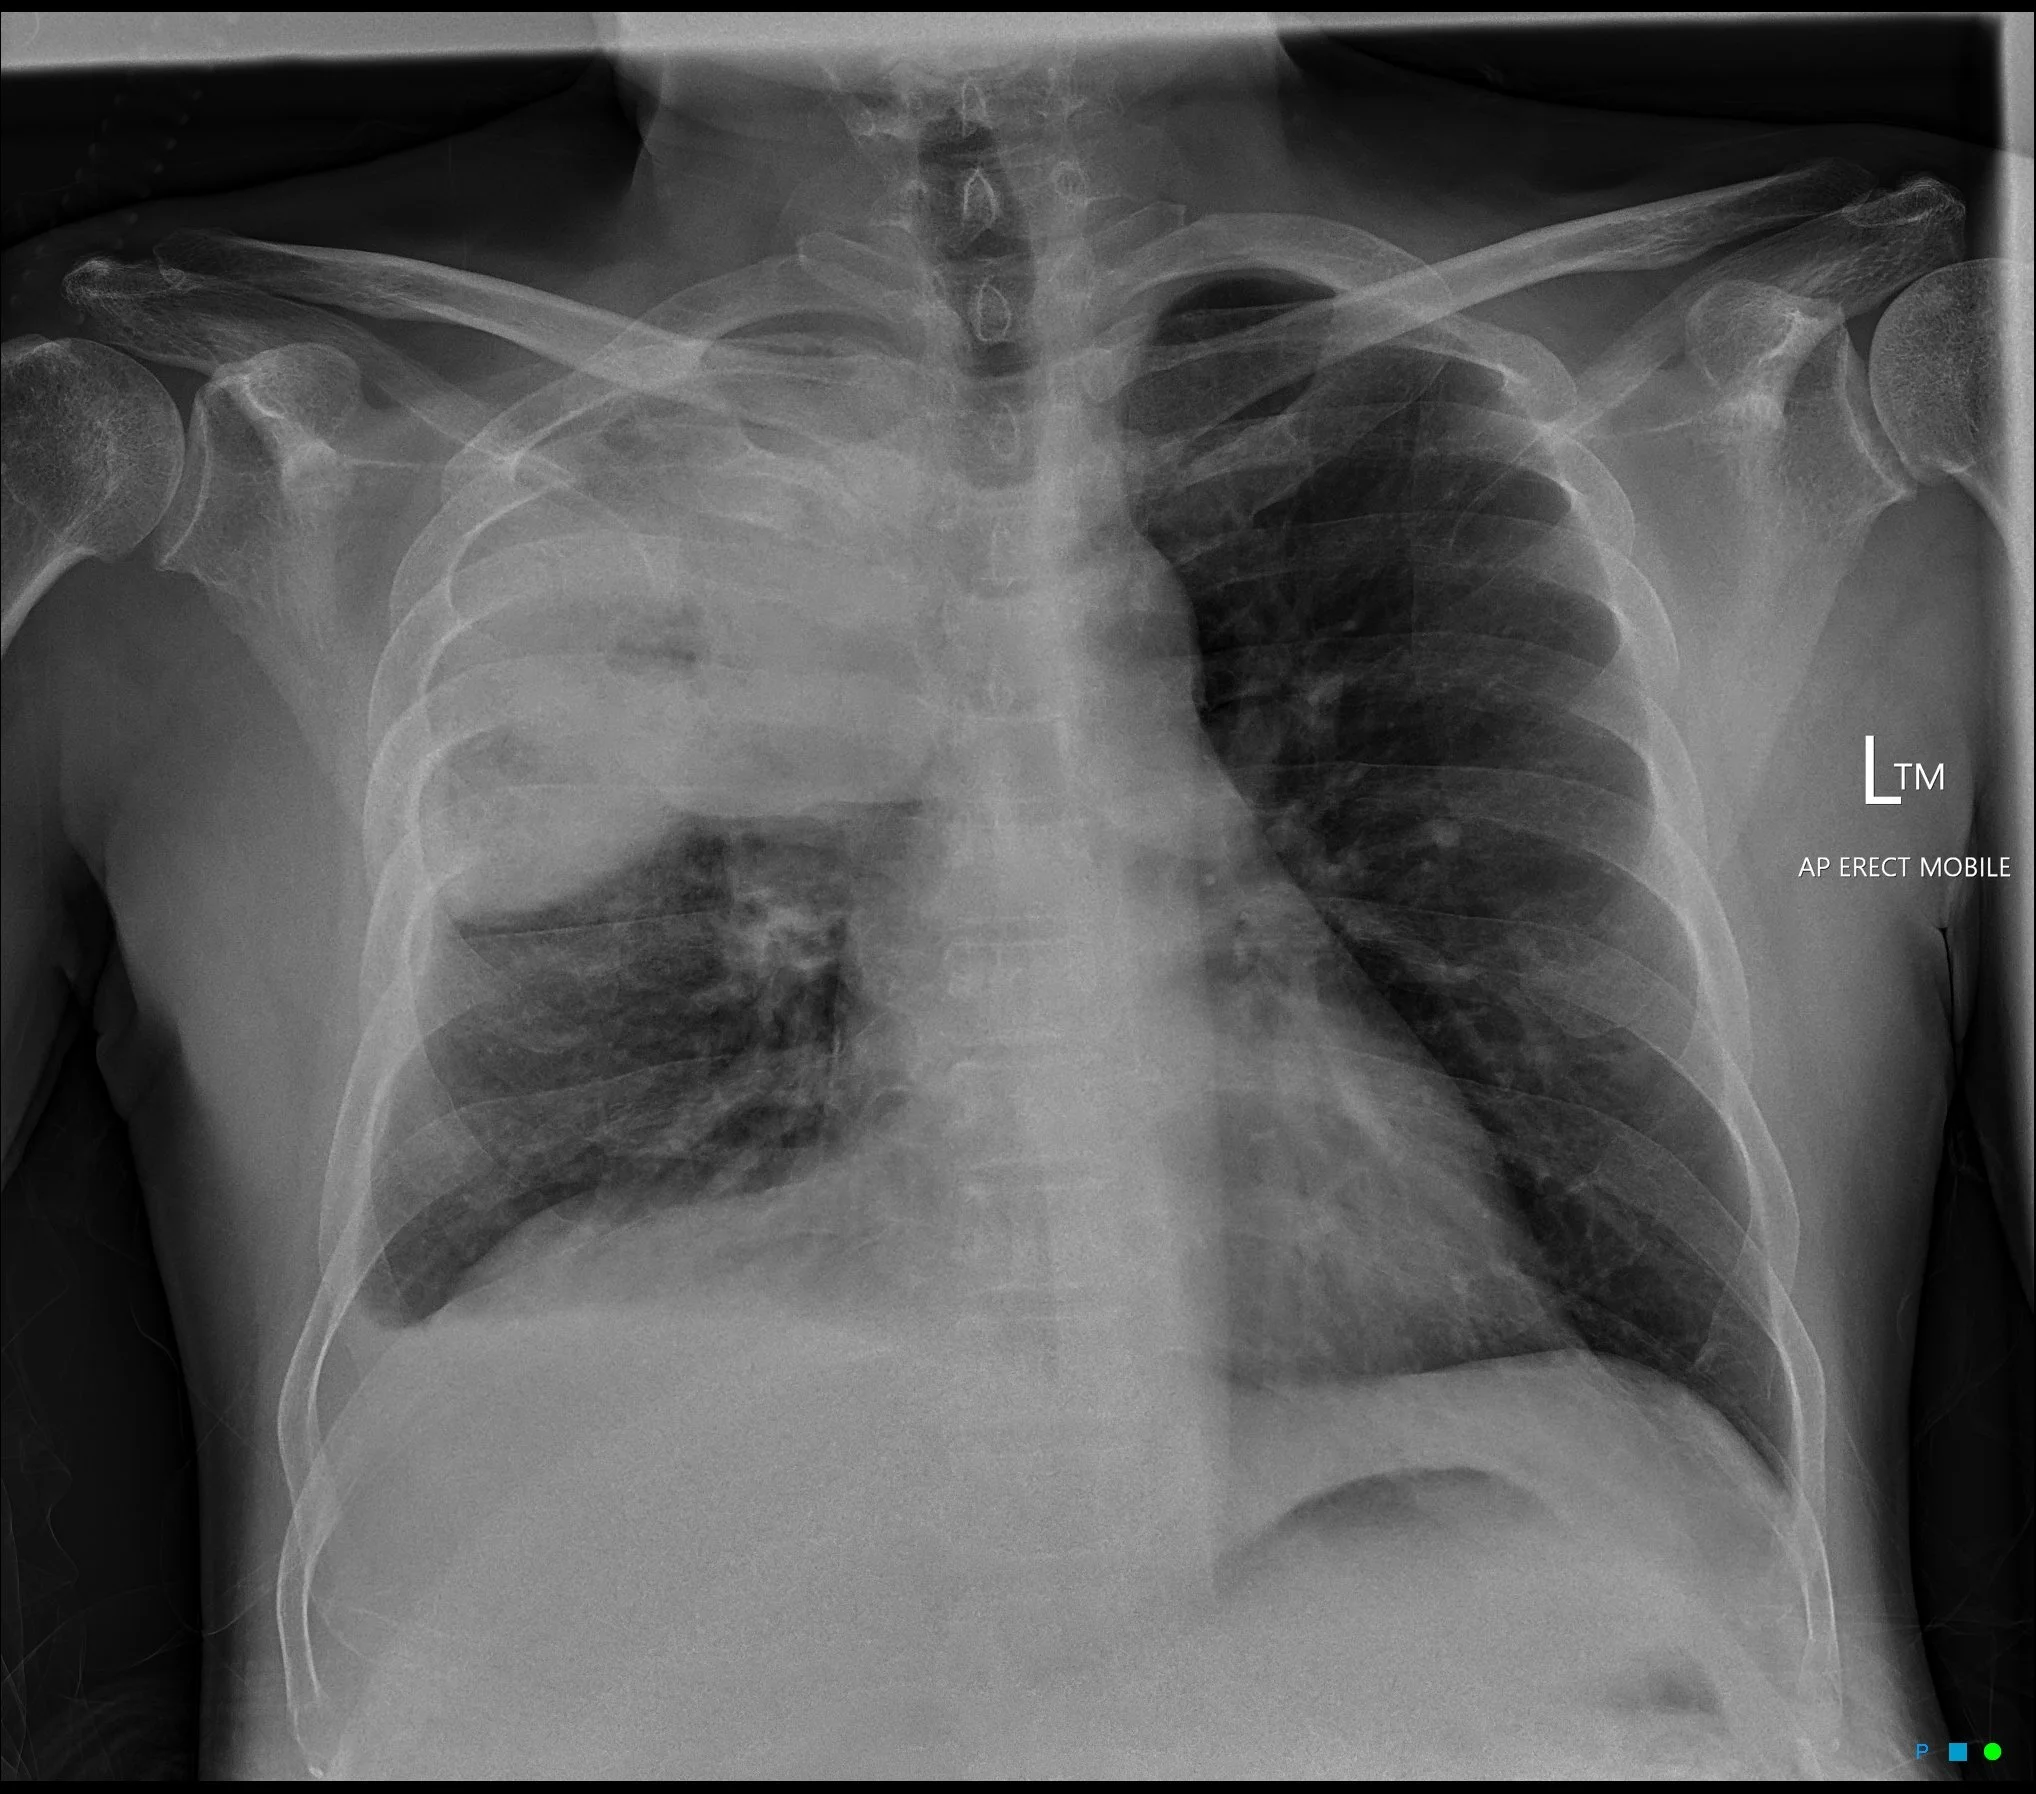

Atoll Sign (Reverse Halo Sign)

• Atoll = circular island with water in the middle (looks like a doughnut)

• Central ground glass opacity with consolidative/enhancing rim

• DDx:

• Cryptogenic organizing pneumonia - main cause

• Fungal pneumonia

• Wegeners (granulomatosis with polyangitis)

• Sarcoid or TB

• Others